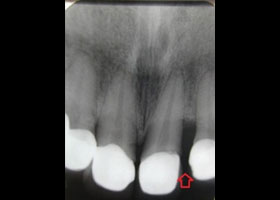

1. 術前口內正面照、局部X光片。

上顎六顆前牙有牙周病,且假牙密合度不佳;下顎有明顯四環黴素染色,造成上下顎色差及美觀問題;且 確實有暴牙。